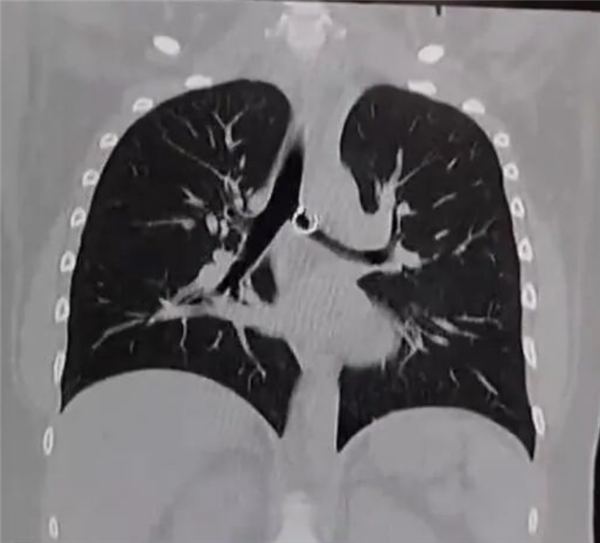

据悉,莫妮卡最初将咳嗽归咎于普通感冒,并未重视,期间发现佩戴的鼻环丢失,也只当是无意中掉落,从未将两者关联。直到咳嗽持续一个月,甚至影响正常生活,她才就医检查,X光和CT扫描清晰显示,其肺部有一枚金属异物,正是她丢失的鼻环。医生检查后直言情况极度危险,鼻环已深深嵌入肺部组织,一端的金属小球距离肺主动脉仅0.5毫米,一旦移位或被触碰,就可能刺破主动脉,导致瞬间大出血,几乎没有抢救时间。

据推测,这枚鼻环大概率是莫妮卡在睡眠中无意识吸入,经气管进入肺部后逐渐移动到危险位置。